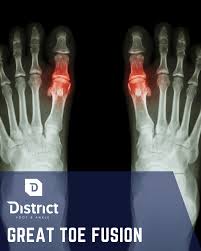

- 무지강직증 — 엄지발가락 관절이 굳으며 움직일 때 통증 발생

| 무지강직증 | 관절 굳음·통증 | 엄지 움직임 제한 |